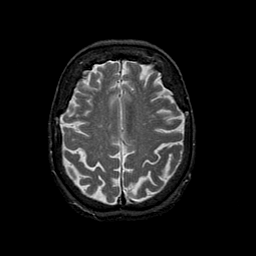

Normal aging, overlay -- Slice #38

[Home][Help][Clinical] Slice 38